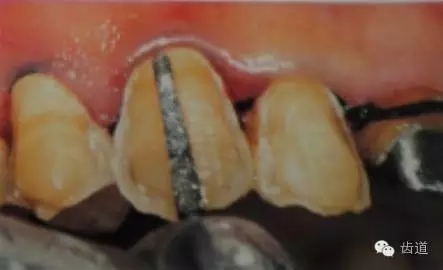

預備齦下邊緣之前要先排齦,之后選用圓頭錐形車針磨除牙體到所設計的邊緣位置。

1)排齦

2)制備